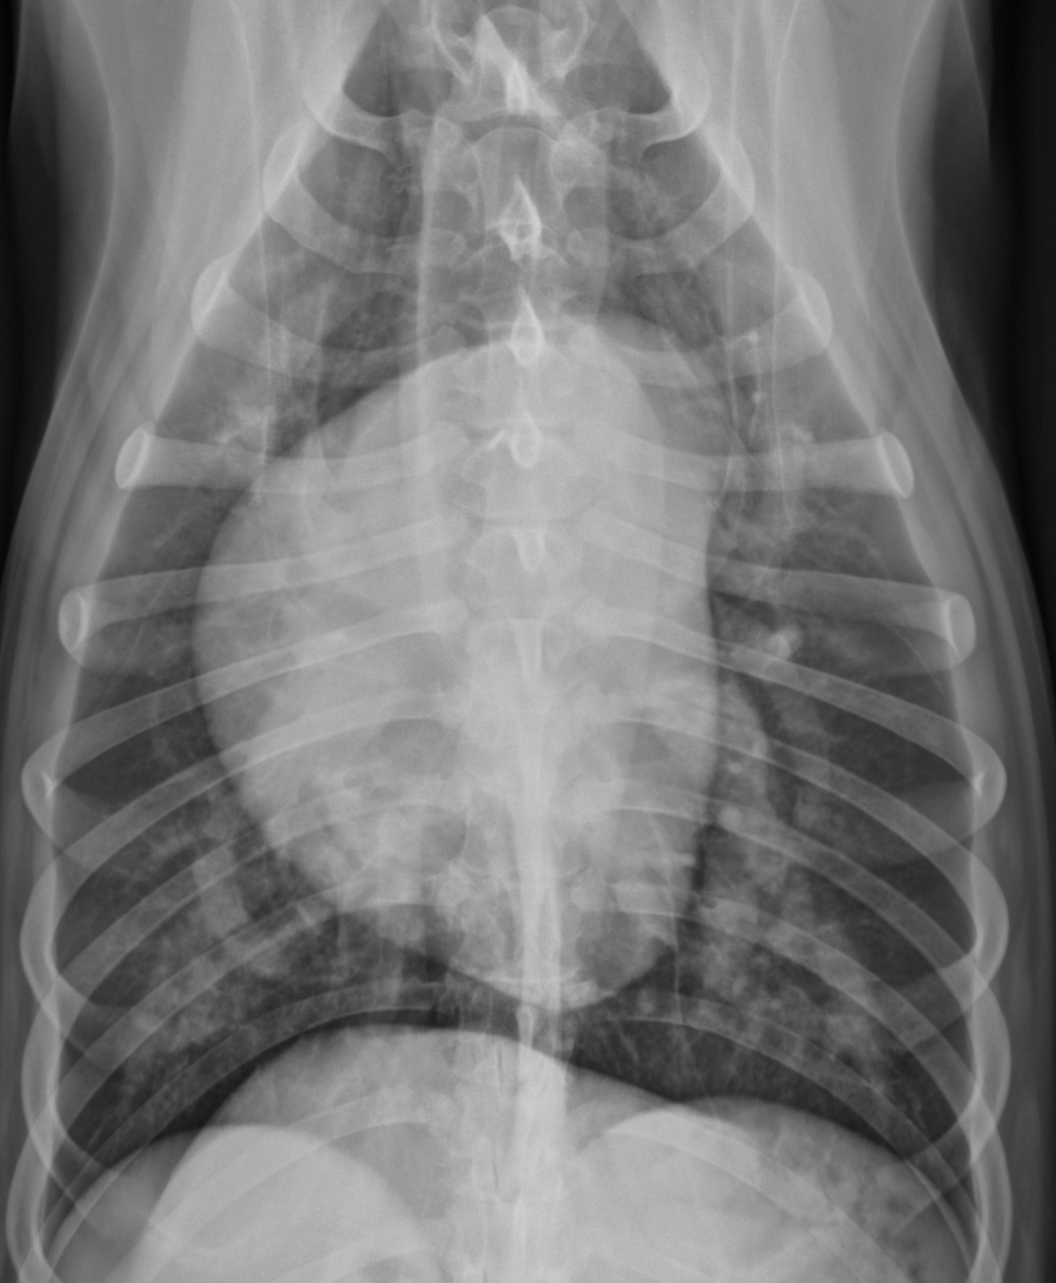

3 features of LAE on DV

-double opacity sign

-separation of main stem bronchi

-LA bulge at 2:30-3 o’clock

What part of the heart is enlarged

LAE